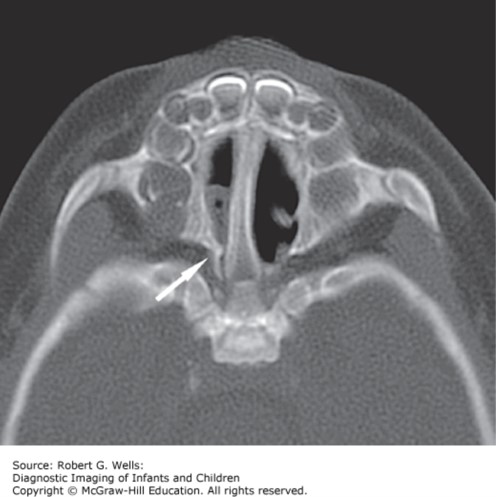

The correct answer is “C.” This patient may have choanal atresia (blocked posterior nasal opening), which is the most common congenital anomaly of the nose and occurs in approximately 1 in 7000 live births. It is typically unilateral and is twice as common in females. Remember that neonates are obligate nasal breathers and anything that creates nasal obstruction (such as choanal atresia) may present as respiratory distress. Option “A” is incorrect because the clinical picture does not fit meningitis. Option “B” is incorrect because you would not expect unilateral discharge with a viral URI. Option “D” is incorrect because you would most commonly see conjunctivitis or pneumonia as a result of neonatal C. trachomatis infection. Although you should think of possible heart failure whenever a young child is having difficulty with feedings, the case description is clearly focusing on an upper airway issue; thus option “E” is incorrect.

Photo: Wells RG. Diagnostic Imaging of Infants and Children; 2015.